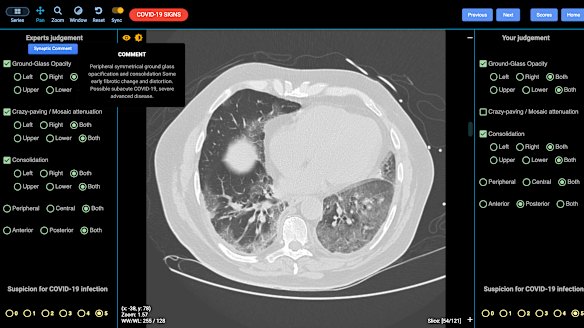

Leading University of Sydney academic radiologist and CovED co-creator Professor Stuart Grieve said there are three predominant signs of COVID-19 that show up on lung scans.

If a patient has the right history of risk, the first sign of an early COVID-19 infection is called “ground glass opacity”, where the normally black space in the lungs appears “like a frosted window”.

The second sign is called “crazy paving”, because Professor Grieve said it looks “exactly like that” - patches of lung that are whiter in appearance than others, which shows a more advanced stage of the disease.

A lung CT showing indications of severe COVID-19.DetectED-X

The third sign is called consolidation, where the lung is filled with mucus and appears white with no air able to enter that area, Professor Grieve said.